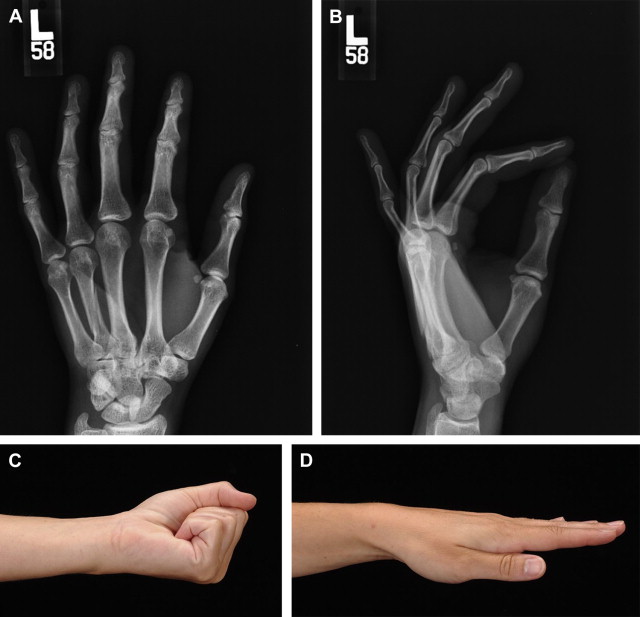

Fig. 1 illustrates a patient that sustained a third metalcarpal spiral fracture that had minimal displacement. The patient wanted surgery, believing it would restore normal function faster. The postreduction with rigid lag screw fixation revealed normal anatomic alignment. The postoperative course, however, was complicated with stiffness that necessitated formal physical therapy. Normal motion was finally obtained but somewhat prolonged (see Fig. 1 ). Similar fractures can be treated conservatively with rapid return to full activities ( Fig. 2 ). Metacarpal neck fractures tolerate conservative management extremely well ( Fig. 3 ). Even metacarpal shaft fractures can be treated in a conservative fashion despite significant dorsal angulation ( Fig. 4 ). These patients must initiate aggressive early motion to maintain normal function. The dorsal hump is usually cosmetic and does not foster physical limitations. Occasionally a palmar prominent metacarpal head can cause tenderness on gripping objects, but this is also uncommon. Multiple metacarpal fractures can also be treated nonoperatively with early active motion ( Fig. 5 ). The key to success is demonstrating normal motion with no scissoring or malalignment and regular follow-up visits. What defines stability of a fracture is an interesting concept. Fractures can be significantly displaced and considered unstable yet still heal with normal function with a conservative approach ( Fig. 6 ). Clinical studies defining the extent of the displacement that will compromise healing or function still need to be done.